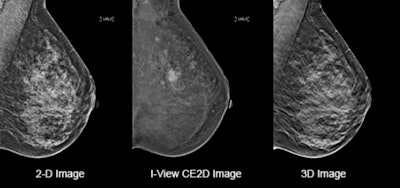

CEM pairs 2D and tomosynthesis images, all under one compression, providing anatomical and functional imaging in one exam.3 The modality leverages a contrast agent, similar to what is used in CT technology, and it accumulates where lesions are forming and growing. For radiologists unfamiliar with CEM, the resulting images can present as a challenge, requiring them to effectively integrate a variety of data points across multiple images for accurate diagnosis. They must acclimate to this new workflow.

Clinical patient images comparing details available on a 2D mammography system (left) with contrast-enhanced software (center) and on a 3D mammography gantry (right). Figure courtesy of Hologic.